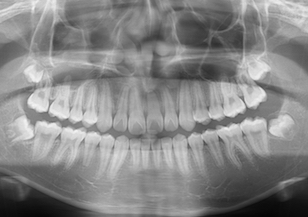

左側上顎の中切歯が埋伏しております。(Before Ⅱの写真は治療前のパノラマレントゲン写真です。)

After Ⅳの写真は治療終了時のパノラマレントゲン写真です。